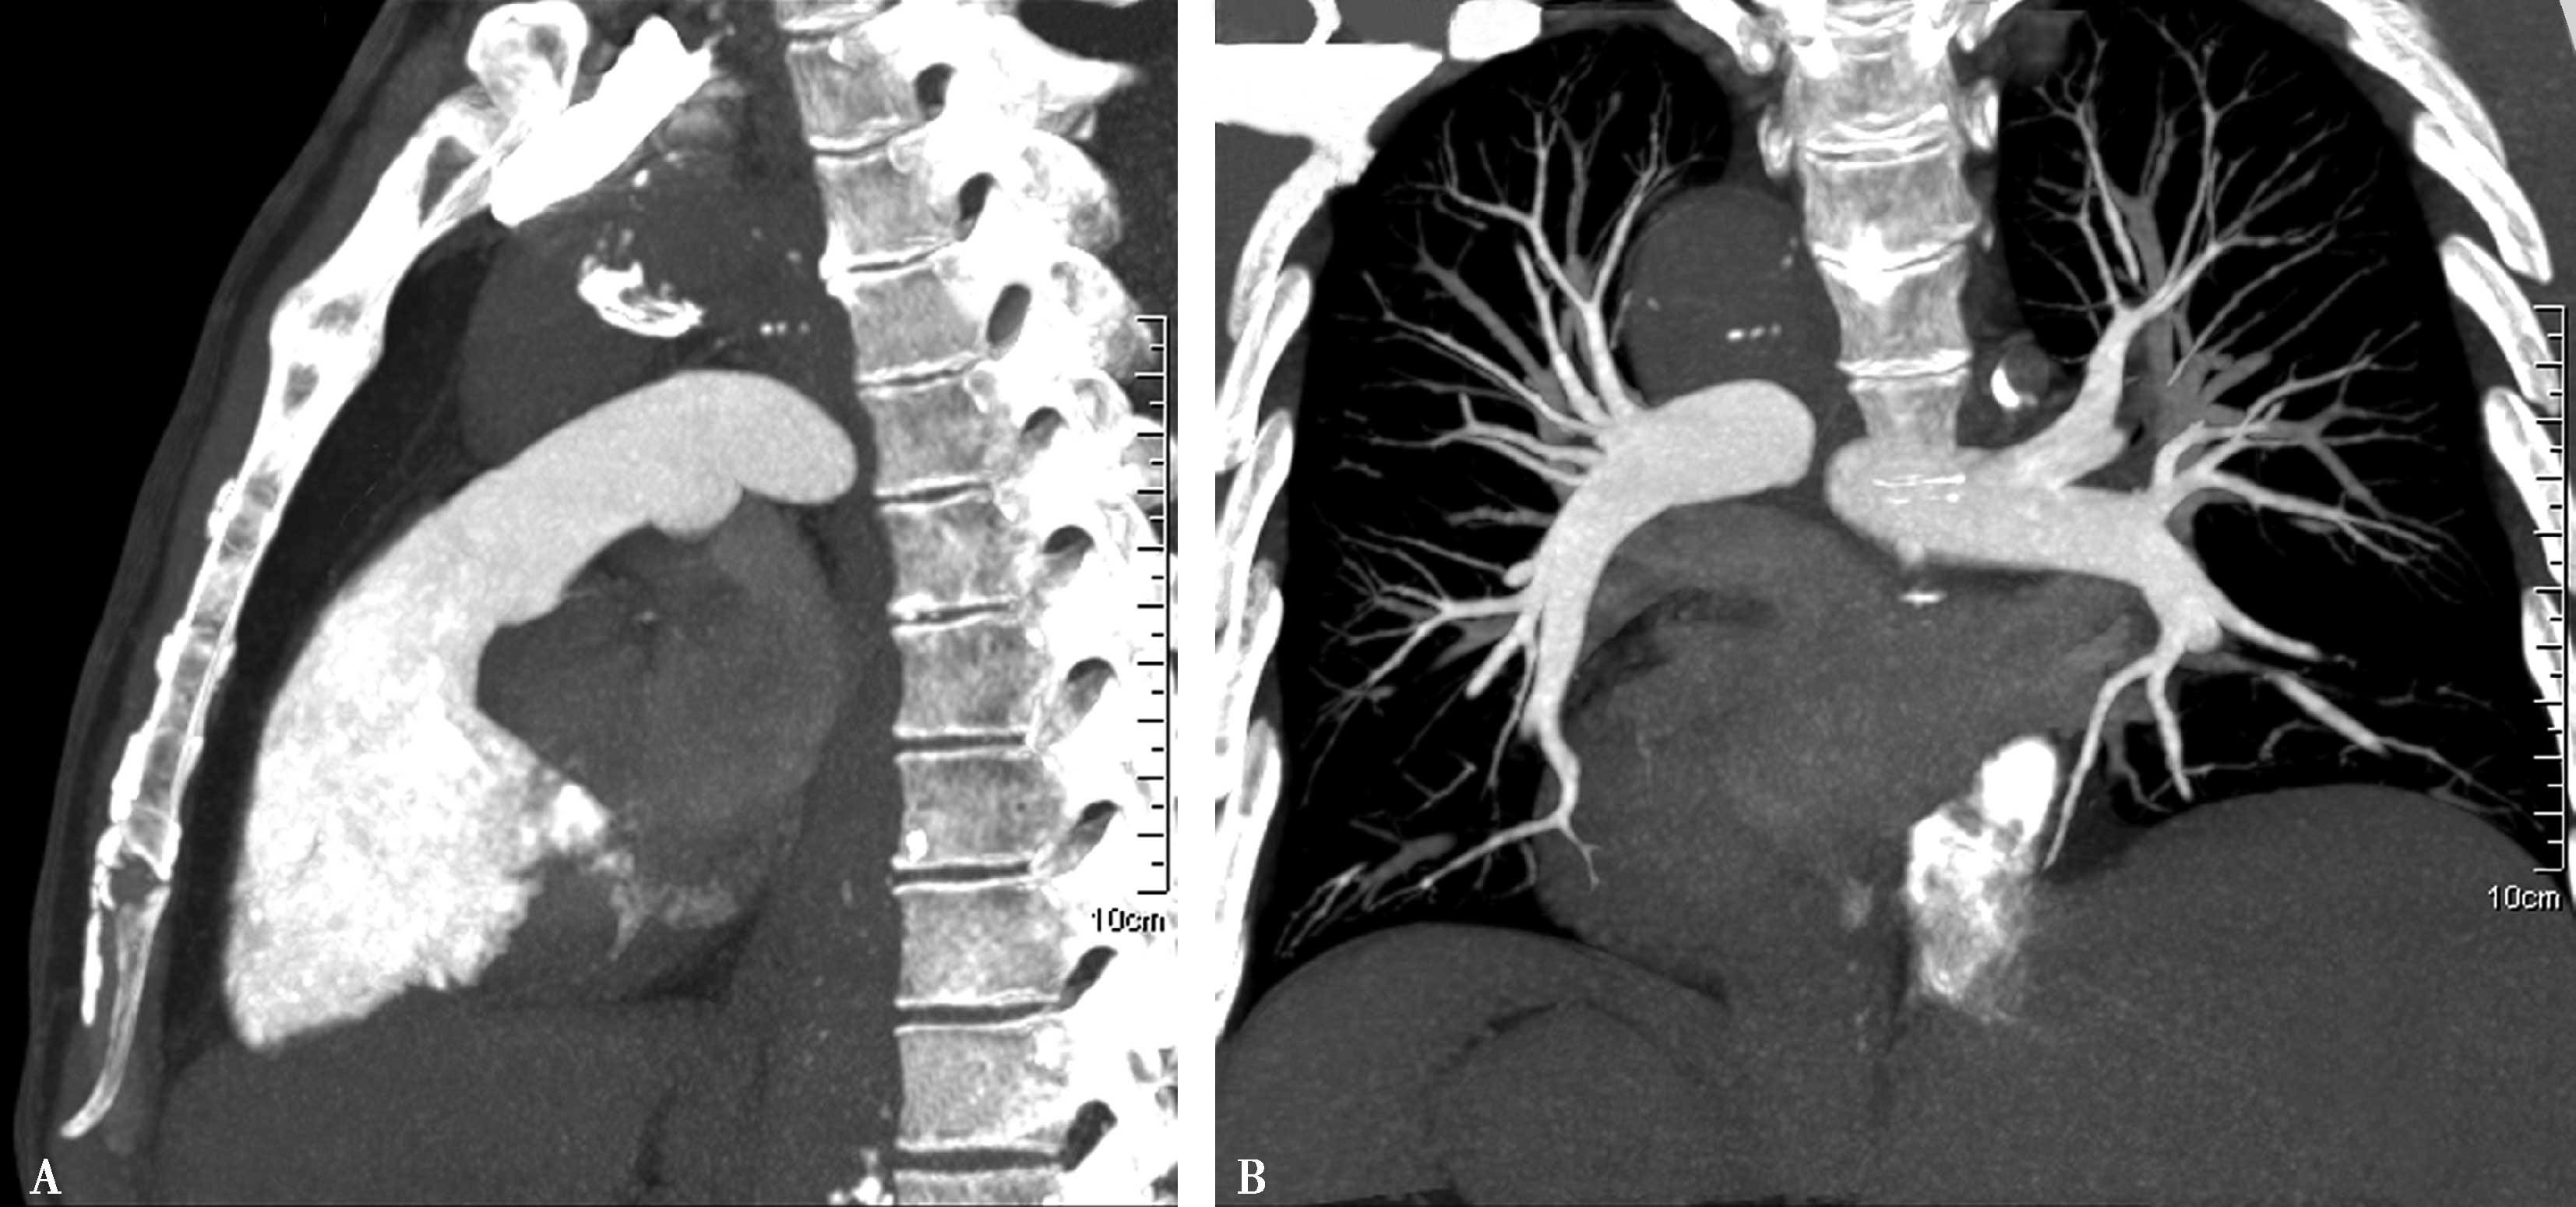

(二)肺静脉解剖

1.横断图像(图8-2-10)

图8-2-10 肺静脉横断像

A.升主动脉层面;B.主动脉根部层面;C.左心房-二尖瓣层面;D.左心房-二尖瓣层面。RSPV:右上肺静脉;RIPV:右下肺静脉;LSPV:左上肺静脉;LIPV:左下肺静脉;LA:左心房

2.曲面重组(CPR)(图8-2-11)

图8-2-11 肺静脉曲面重组

A.右上肺静脉(RSPV↑);B.右下肺静脉(RIPV↑)